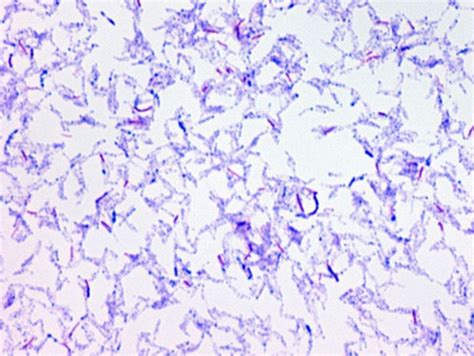

Identifying Acid Fast Bacteria involves specific staining techniques that highlight their unique properties. The most commonly used method is the Ziehl-Neelsen stain, which involves the following steps:

• Prepare a smear of the bacterial sample on a microscope slide.

• Heat-fix the smear by passing it through a flame.

• Stain the smear with carbol fuchsin for about 5 minutes.

• Decolorize the smear with acid-alcohol for 2-3 minutes.

• Counterstain with methylene blue or malachite green for 1-2 minutes.

• Wash the slide with water and observe under a microscope.

Acid Fast Bacteria will appear red or pink due to the retention of carbol fuchsin, while other bacteria will be counterstained blue or green.